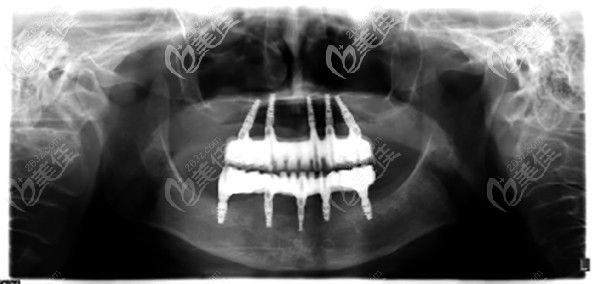

關(guān)醫(yī)生就此跟阿姨科普了一下“滿口無牙患者不一定非要全口種牙,只要種植的基牙能夠滿足日常用牙需求即可。具體種多少顆牙,要看個(gè)人口腔狀況及全身狀況”,“那么根據(jù)阿姨您的這種牙齒情況,屬于牙齦牙槽骨萎縮+骨量不足,所以建議做上下各5顆種植”。

之后關(guān)醫(yī)生拿著阿姨的片子,詳細(xì)分析她的牙齒情況,然后介紹給出這種種植方案的優(yōu)勢(shì)在哪,不影響她晚年享受美食的樂趣。